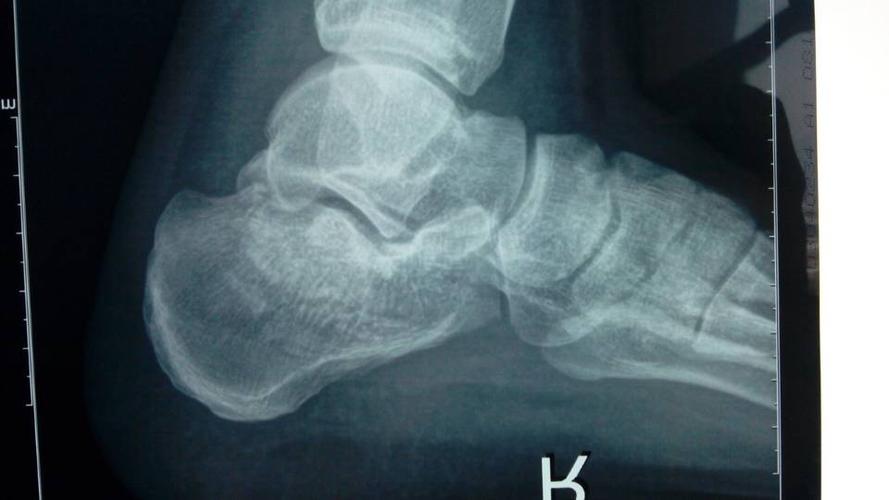

跟骨轴位(被检者坐于摄影台,被检侧下肢伸直,足尖向上,稍内旋,踝关节